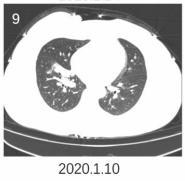

下面这个患者,右下叶病灶,既无磨玻璃,又不在胸膜下,依靠CT诊断新冠肺炎几乎不可能。